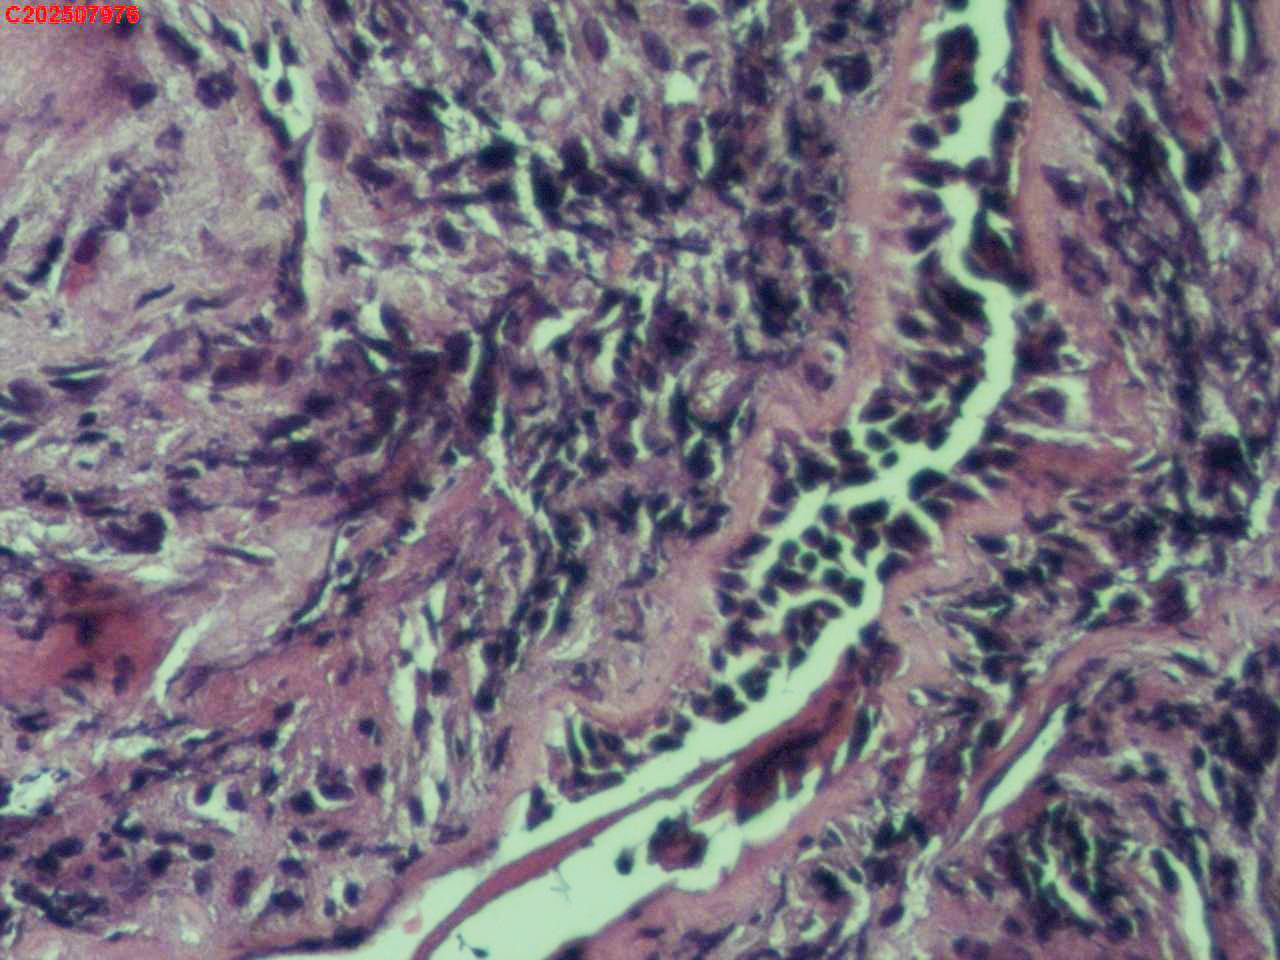

右肺上叶开口处 气管镜咬检

右肺上叶开口上缘处可见肉芽增生,予咬检。

感觉:炎性纤维组织增生